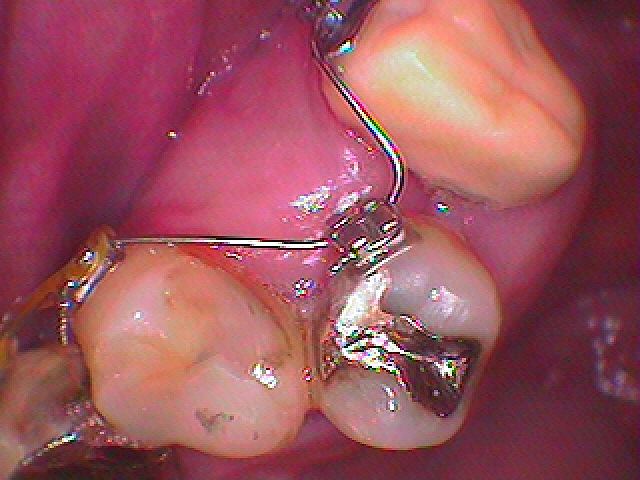

MTMによる矯正治療。| |広島市安佐南区の歯科医院 MTMによる矯正治療。 トップ お知らせ・ブログ MTMによる矯正治療。 MTMによる矯正治療。 Web診療予約 初めての方へ 選ばれ続ける理由 院内設備について 歯が痛いしみる一般歯科 歯がぐらぐらする歯周病 健康な歯を保ちたい予防歯科 子供の虫歯予防をしたい小児歯科 銀歯をセラミックに審美歯科 白い歯を目指しませんか?ホワイトニング 矯正専門医がいるので安心矯正歯科 抜けた歯を補いたいインプラント・入れ歯 医院案内 スタッフ紹介 メリィハウス歯科クリニックオフィシャルホームページ ラベンダー歯科クリニックオフィシャルホームページ お知らせ・ブログ ホーム 診療科目 一般歯科 歯周病治療 予防治療 小児歯科 審美治療 ホワイトニング 矯正歯科 入れ歯・インプラント マウスピース矯正 初めての方へ 院長・スタッフ 設備紹介 医院案内・アクセス メニューを閉じる